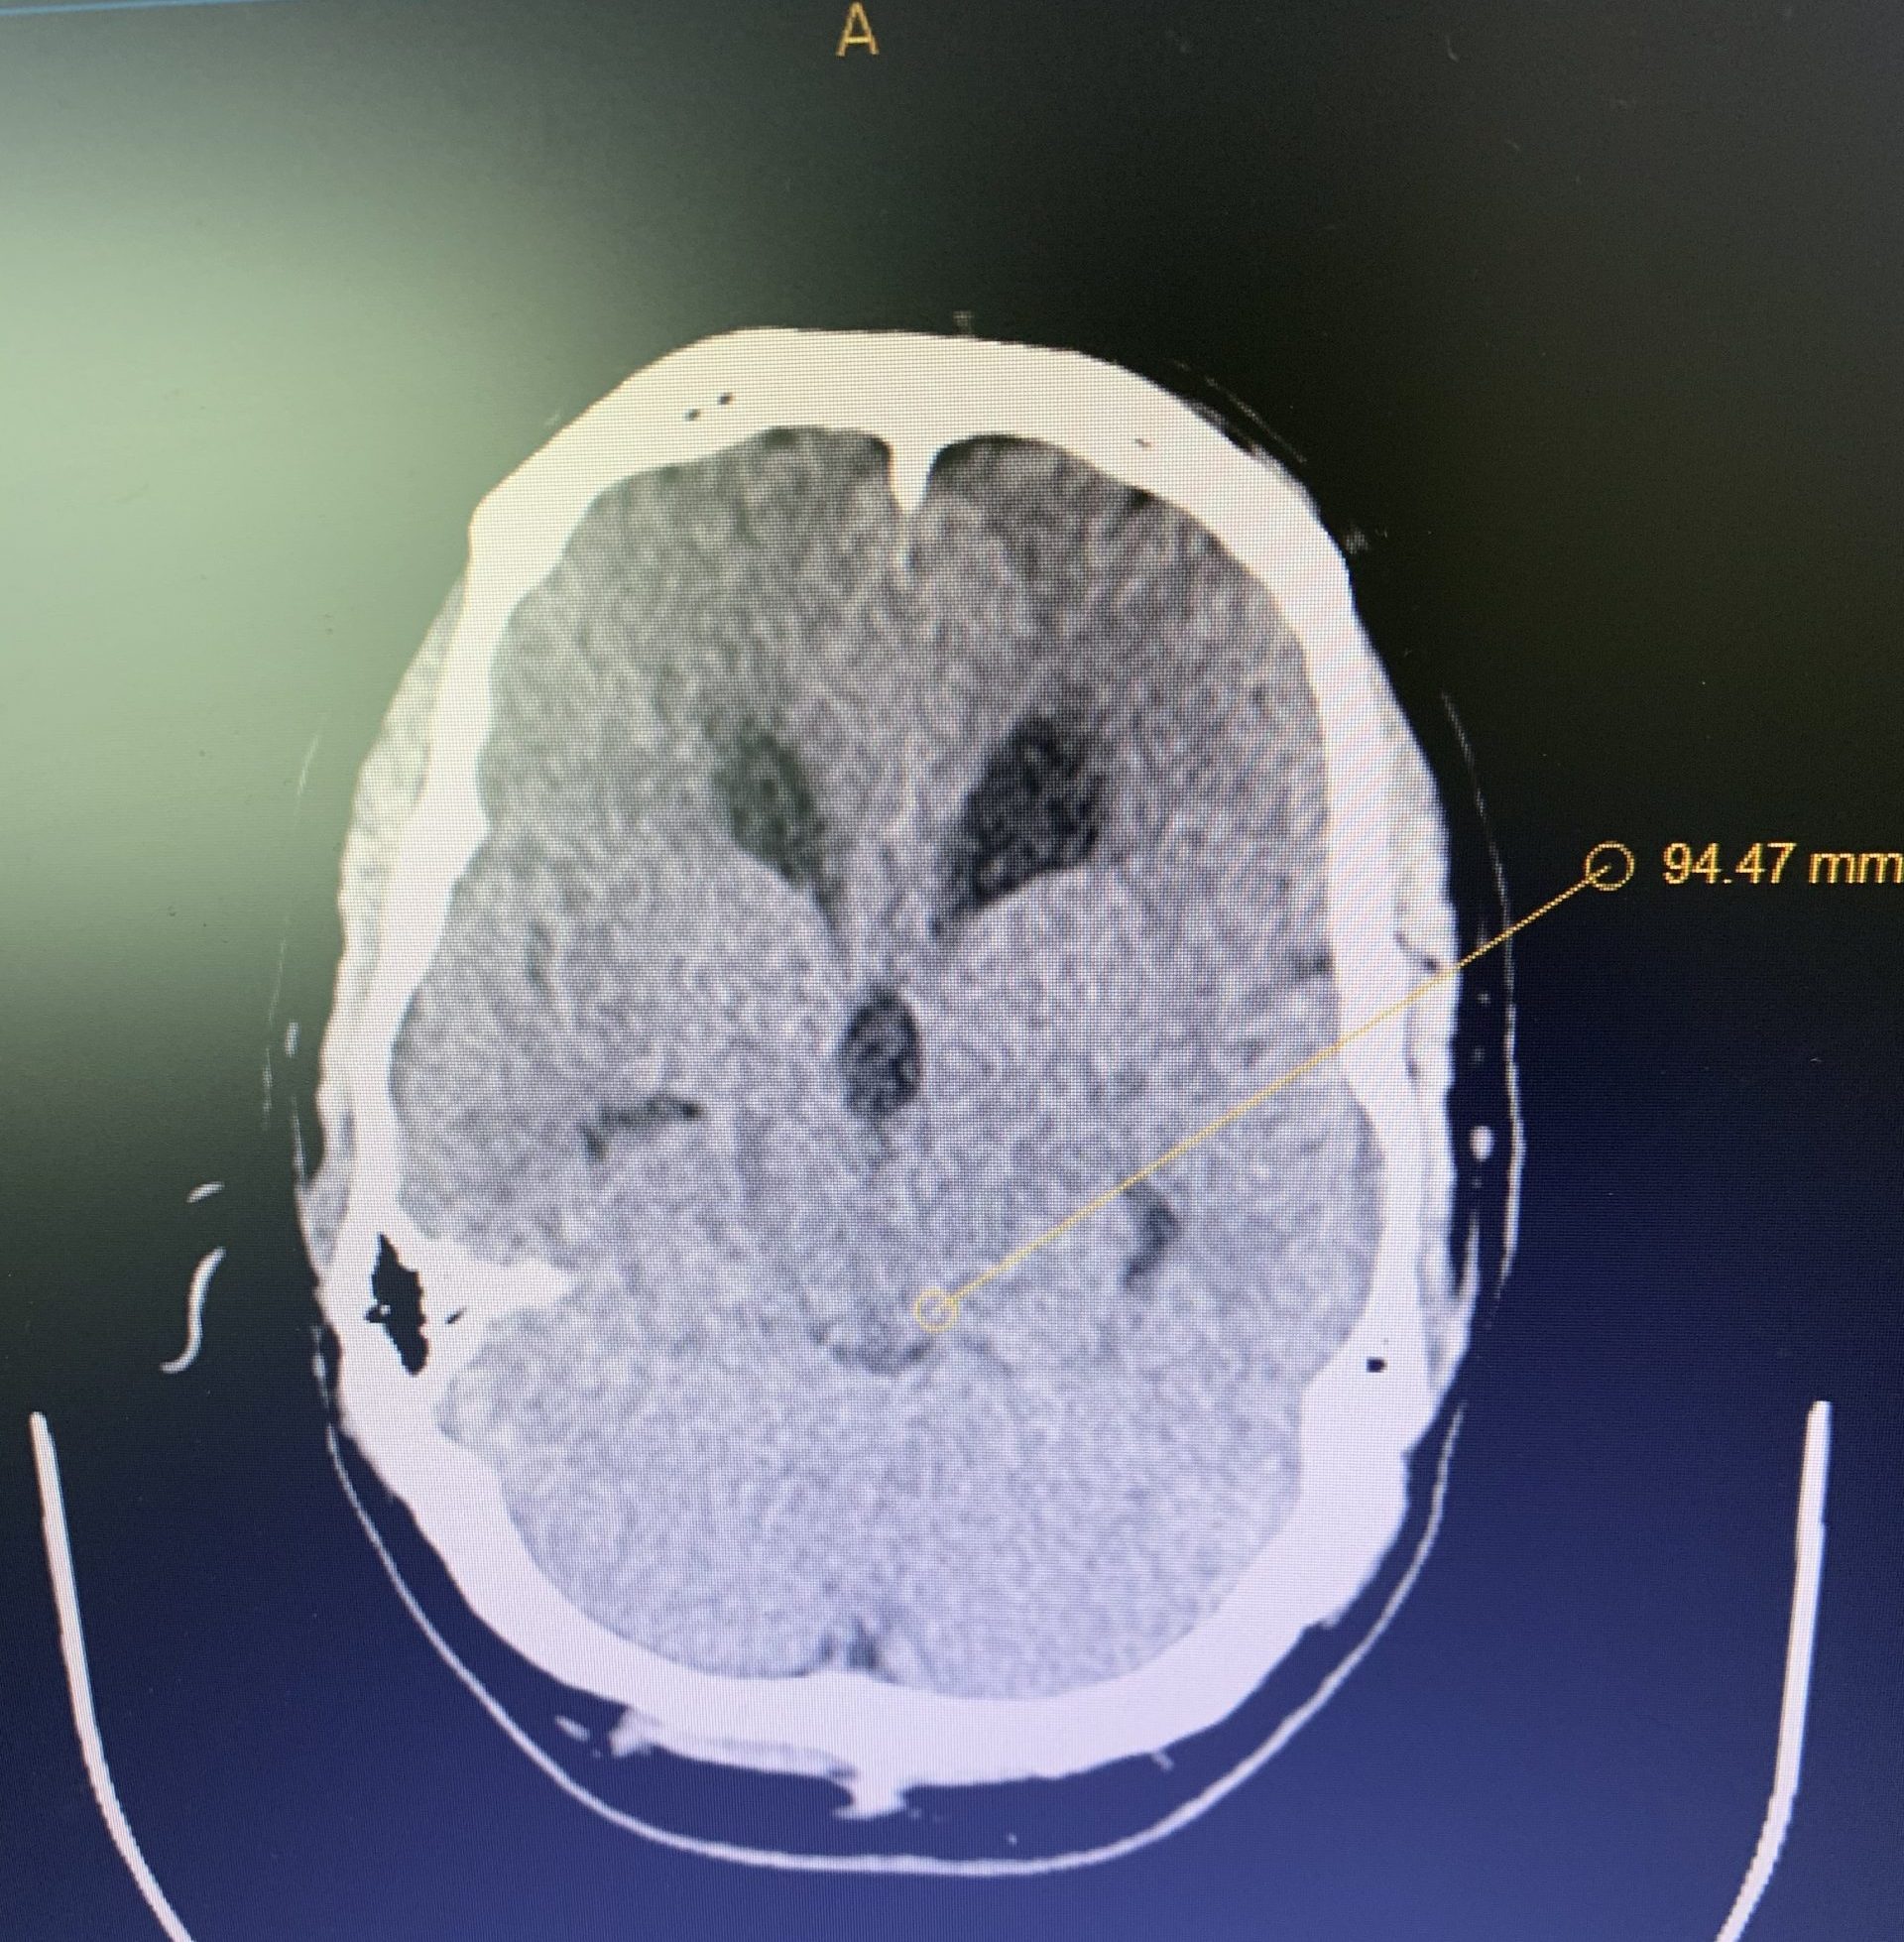

Imaging and other provocative diagnostic test showed the associated problems of Cranial Cervical Instability, incidental thoracic syringomyelia, Hashimoto Thyroidistis, Polycystic Ovarian Syndrome, Nutcracker Syndrome, Postural Orthostatic Hypotension, and Hypo/Hyper intracranial Pressure with spontaneous CSF leaks.

Her symptoms of Intracranial hypotension have been challenging.

As in her case, MRI imaging, with heavily weighted T2 Fat-Saturated Sequences (3D-T2WI-FS) provide a very high accuracy for the CSF leak presence into the epidural space. Multiple imaging sites are usually identified, although at surgery or with dynamic CT myelography, only one site is found.

The thin Dura in patients with EDS can dehisce at any point. Other causes include on osteodiscophyte penetrating the Dura, or rupture of a spinal nerve root diverticulum. Recent appreciation of other mechanism of Spontaneous Intracranial Hypertension (SID) includes CSF-Venous Fistula.

High Volume Blood patches under X-ray guidance, with a very small needle, being careful not to puncture the dura is indicated. This usually give relief lasting days to months. It may well need to be repeated.

Injection of fibrin glue into the epidural space, has a much greater chance of healing the CSF leaks. However, it can also impair “normal” CSF dynamics in these abnormally compensated situations, leading to intracranial hypertension.

Spontaneous Intracranial Hypotension (SIH) associated with EDS is often a complex disease. I am thankful to be part of a strong team that can address the plethora of problems these patients face.